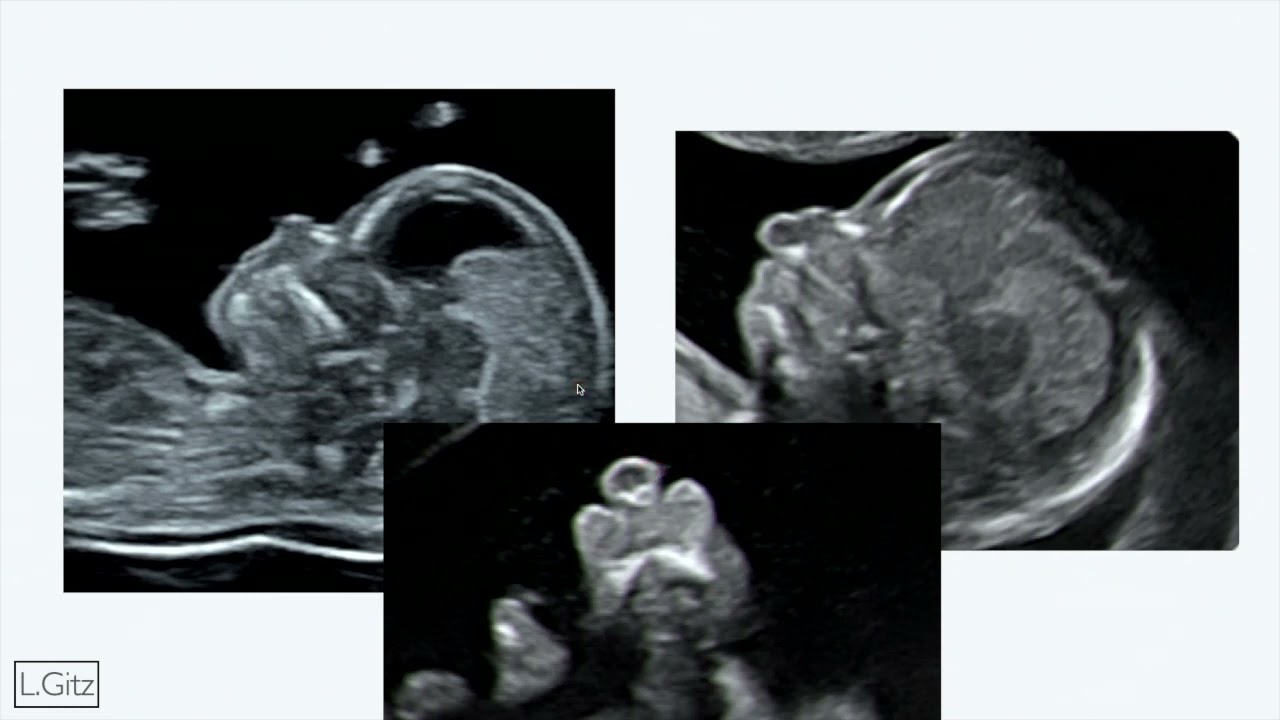

Thème abordé : C'est une vidéo à propos du retard de croissance intra-utérin.

Le troisième trimestre, c'est le trimestre où l'on va faire une échographie pour s'assurer que le bébé grandit bien.

Alors typiquement, vous savez qu'il y a un retard de croissance intra-utérin par ce qu'au cours de votre échographie, votre médecin va vous dire, "oh la la, bah dis donc, le bébé il est un petit peu petit, il ne grandit pas très bien, il y a un retard de croissance intra-utérin".

Alors, on va essayer de mettre les choses au clair, parce que ça peut être un petit peu effrayant comme terme, on dit, "oh la la, mince, mon bébé ne grandit pas".

Dans cette vidéo, nous allons essayer de vous expliquer au mieux, qu'est-ce que le retard de croissance, et qu'est-ce que ça implique réellement.